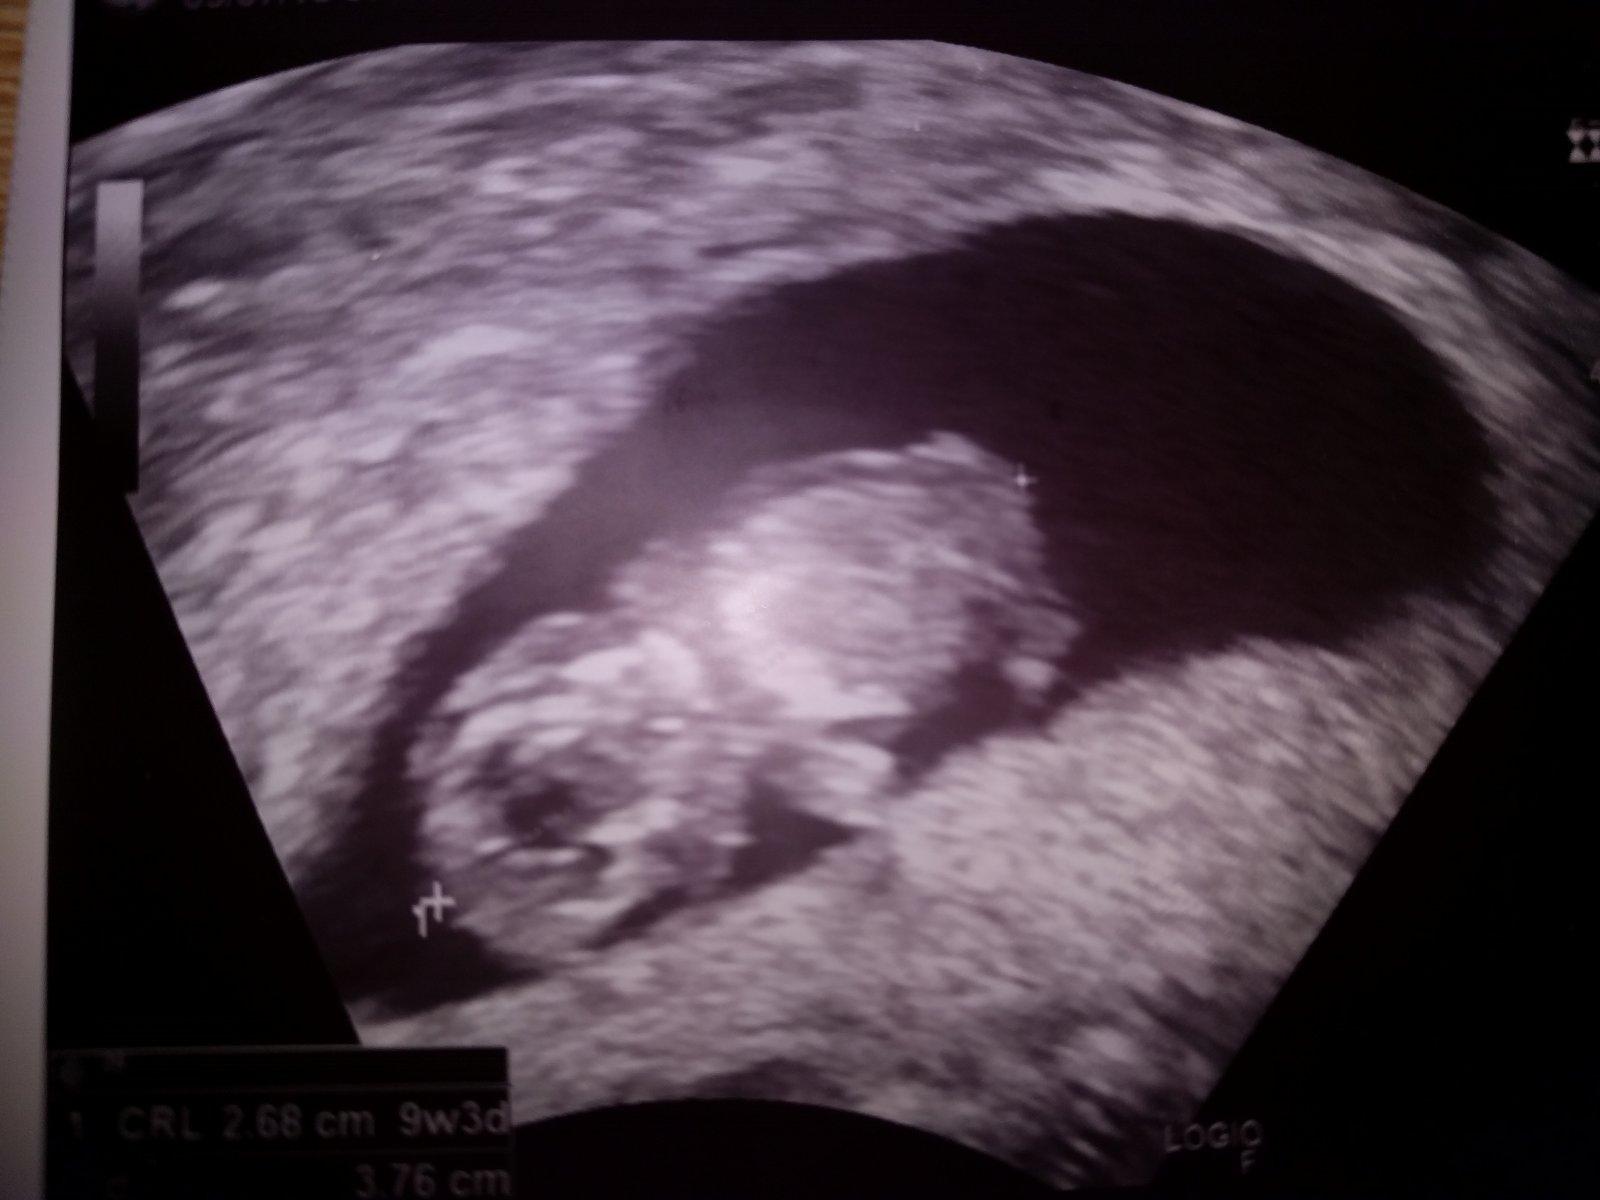

@veronika_2019 v těch 9+3 měl od hlavičky po kostrč 2,68 cm 🙂 pevně doufám, že dneska v 10+4 už má o dost víc 😀

@veronika_2019 Miminko měří 2,86 cm. A předpokládaný termín porodu vychází na 8/2